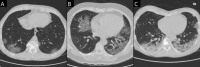

Figures